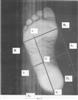

Сущность изобретения поясняется чертежами: на фиг.1 сканографическое изображениями стопы; на фиг.2 образец разметки стопы с целью диагностики их состояний; на фиг.3 – шаблон паспортных данных и результатов обследований; на фиг.4 – подбор вариантов заключений из таблицы результатов. Используются сертифицированные аппаратные и программные средства: компьютер PC Pentium II или выше с установленной лицензионной операционной системой Microsoft Windows XP, и программой Abbyy Fine Reader 7.0 или выше, планшетный сканер, при необходимости – принтер и мерная линейка.

2. Производится сканирование подошвы стоп. Снимки стоп показаны на фиг.1.

3. Оператор производит разметку изображения стопы (фиг.2).

Алгоритм анализа следующий:

На каждом из снимков стоп оператор выделяет мышью точку, соответствующую головке пятой плюсневой кости – точку В. После этого – точку пяточного угла – А1, проводится линия, соединяющая эти точки.

Оператор выделяет мышью на изображении стопы точку, соответствующую головке первой плюсневой кости – точку В1. После этого – проводит прямую ВВ1.

Оператор устанавливает на изображении точку О на границе соприкосновения с опорой внутреннего контура свода стопы.

Оператор проводит через точку О линию аа1 параллельно линии ВА1.

Оператор на изображении стопы проводит линию В1В2 через точку В1 параллельно ВА1. Оператор проводит через точку О линию bb1 параллельно ВВ1. Далее измеряется длина отрезков bb1 и bO. Вычисляется отношение (D) длины отрезков bO к bb1 в процентах. Оператор заполняет шаблон паспортных данных (фиг.3) и вычисляет с использованием таблицы (фиг.4) диагностические показатели для определения состояния стопы с заключительной оценкой: при D40% – заключение «нормальная стопа»; при D>40% и D60% – заключение «уплощение стопы»; при D>60% – заключение «плоская стопа».